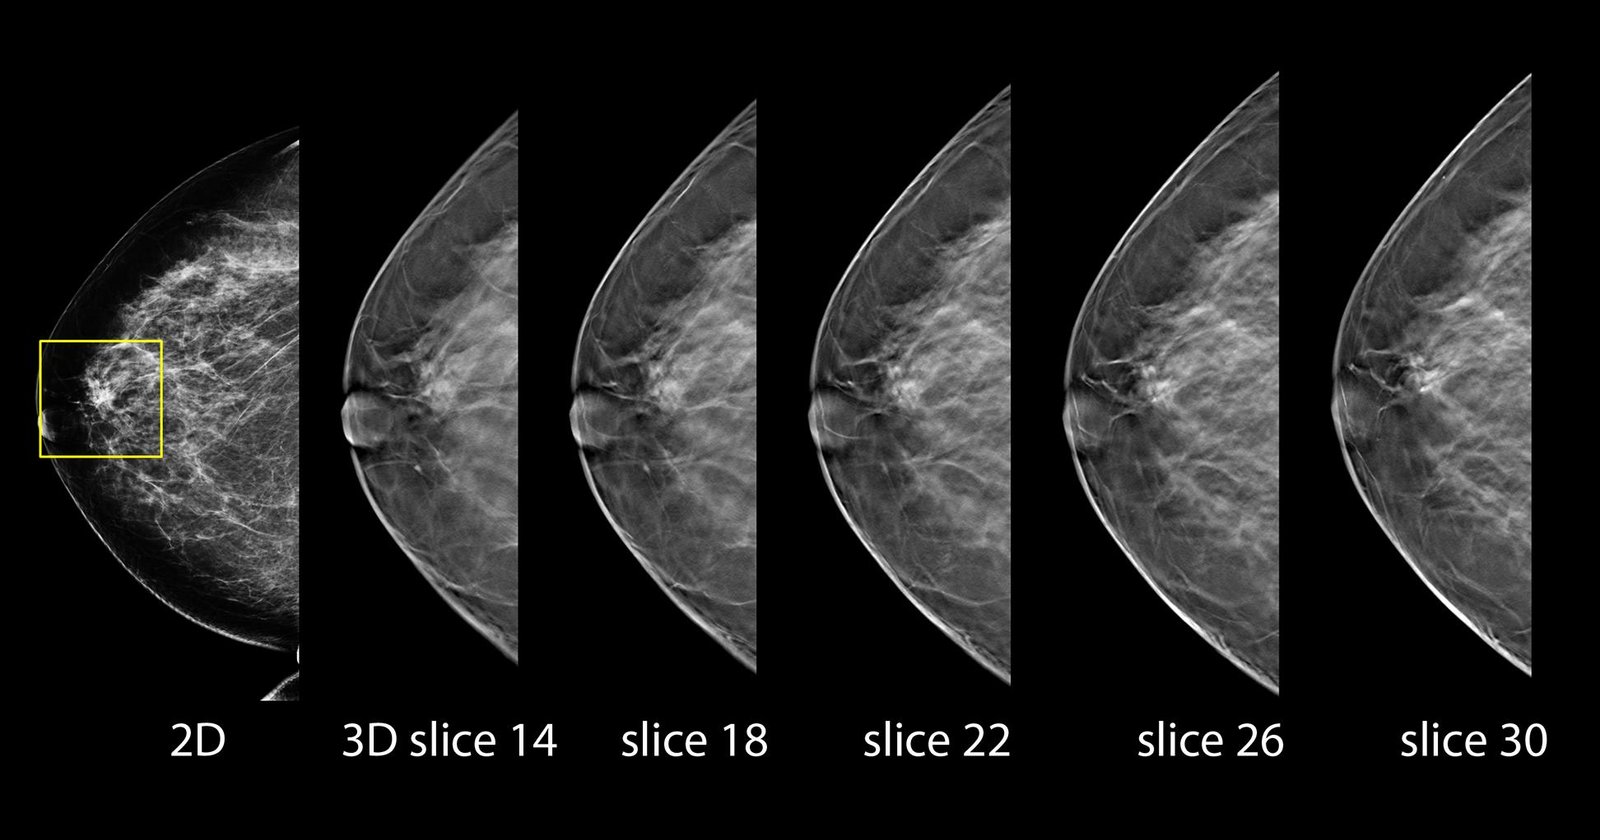

Better visibility

Designed to improve visibility of fine details for greater diagnostic confidence.*

* is compared to 2D alone